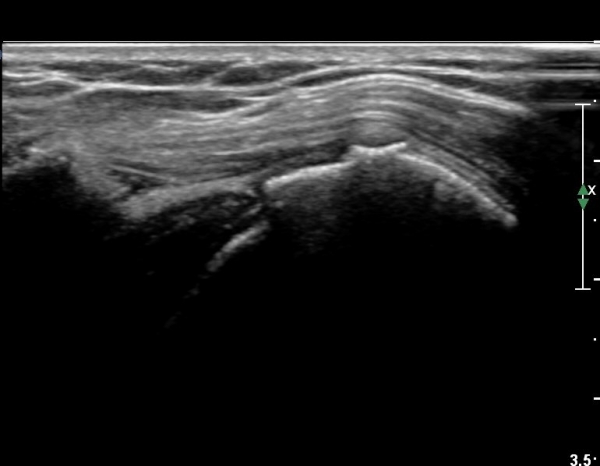

¿ì¼± ¿òÁ÷À̱â ÀüÀÇ ¿µ»ó¿¡¼­ ´ë°áÀýÀÇ °ñ±Ø µ¹Ãâ·Î ¿ïÅüºÒÅüÇÔ°ú ±Ø»ó°ÇÀÇ ÆÄ¿­ÀÌ

°üÂûµÇ°í ¿ÜÀü ½Ã ´ë°áÀý°ú °ßºÀÀÌ ºÎµúÈ÷°í ´ë°áÀýÀÌ »ï°¢±ÙÀ» Ç¥ÃþÀ¸·Î µ¹Ãâ½Ã۰í

°ßºÀ ¿ÜÃø¿¡ ¼ö¾×ÀÌ Àú·ùµÈ´Ù.